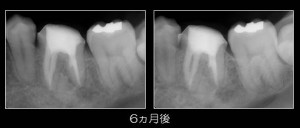

そして、先日6ヵ月後の経過観察で来院していただき・・・

もちろん、経過良好です(^0^)/

歯肉の状態も問題なし!